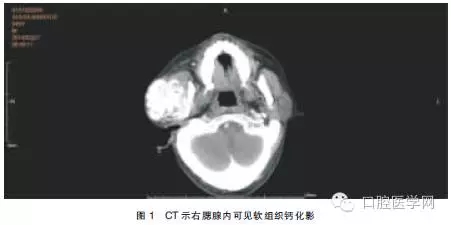

查體:患者面形左右不對(duì)稱,右耳前有一約5.0 cm×5.0 cm大小的軟組織隆起,質(zhì)地較硬,與周圍組織界限不清,無(wú)活動(dòng)度,開口度未受影響。血鈣:2.7mmol/L,血磷:2.9mmol/L,肌酐:953μmol/L,尿素氮:5.7mmol/L。使用GE VCT64排螺旋CT進(jìn)行掃描(球管電流:250mA,掃描電壓:120kV,周期:0.4s/周,層厚:5mm),掃描范圍:顱底至頸根部。結(jié)果示:右腮腺區(qū)見團(tuán)塊狀混雜密度(軟組織內(nèi)伴鈣化)影,邊界欠清,與腮腺組織及血管分界不清,與咬肌及周圍骨結(jié)構(gòu)分界欠清(圖1)。